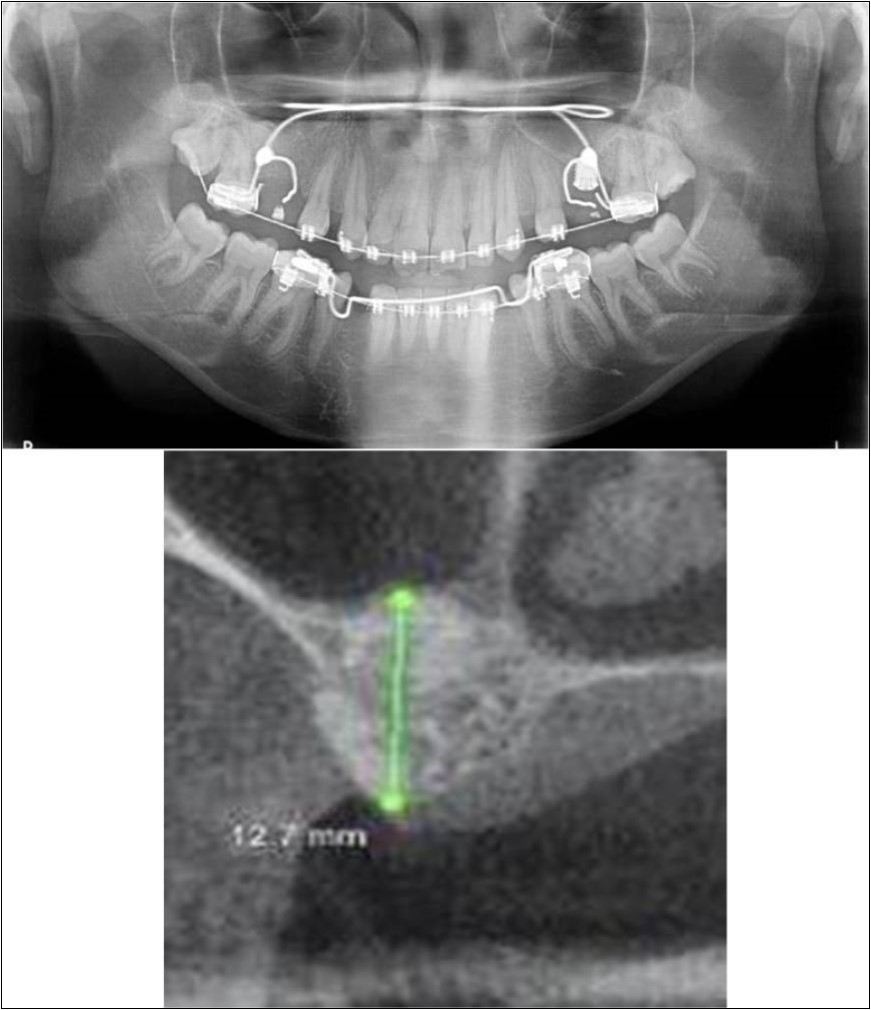

Treatment:

Patient underwent the procedure of indirect sinus elevation using sinus osteotomes in relation to 26 region. Calcium phosphosilicate putty was dispensed as the graft material through the crestal osteotomy site to maintain the elevated sinus membrane followed by placement of 5 x 10mm dental implant under local anaesthesia and strict aseptic protocols. The implant was allowed to osseo-integrate for a period of six months during which the patient was followed-up periodically and was assessed for peri-implantitis, crestal bone loss and mobility. Patient was taken-up for direct sinus elevation via lateral window approach for sinus augmentation i.r.t 16 region. Under aseptic conditions and local anaesthesia, lateral wall of maxilla was exposed after muco-periosteal flap elevation. A window was created of 1cm diameter corresponding to apical aspect of 16. Sinus membrane was identified and elevated using sinus elevators and reamers without perforating the lining. Once the sinus membrane was elevated, phosphosilicate putty was dispensed through the lateral osteotomy site as the graft material to achieve an augmentation of 1cm assessed clinically and confirmed using post-operative OPG. At the end of 6 months, a repeat CBCT scan was advised to evaluate the increase in bone height. (Figure 13a,b, pre-treatment; Figure 14a,b, post-treatment)

Figure 13.(a,b) Pre-treatment OPG and cross section of CBCT showing residual alveolar bone height for Case No.4;

Figure 14.(a,b) Post-treatment OPG and cross section of CBCT showing residual alveolar bone height for Case No.4;